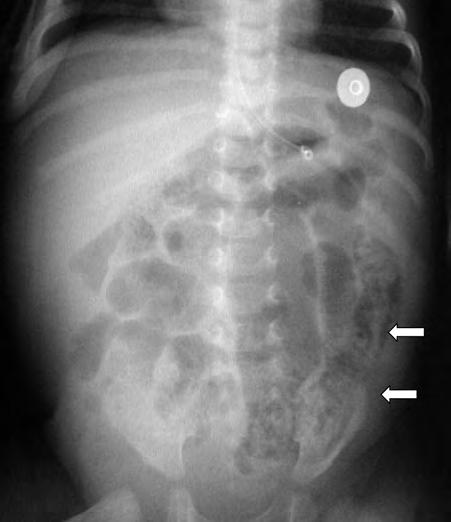

La sospecha clínica de ECN se confirma mediante estudios radiológicos seriados. La dilatación intestinal generalizada es el signo radiológico más precoz. Puede presentar otros signos inespecíficos iniciales como el engrosamiento de la pared de las asas intestinales o la presencia de líquido libre en el peritoneo. De modo más tardío, pueden observarse signos más específicos de ECN como la neumatosis intestinal (aire intramural) (Fig. 2.24.2).

Es importante comprobar la presencia de otros signos radiológicos que pueden indicar una evolución tórpida con presencia de un asa intestinal fija, extensión de la neumatosis a la circulación venosa portal o la presencia de neumoperitoneo (Fig. 2.24.3).